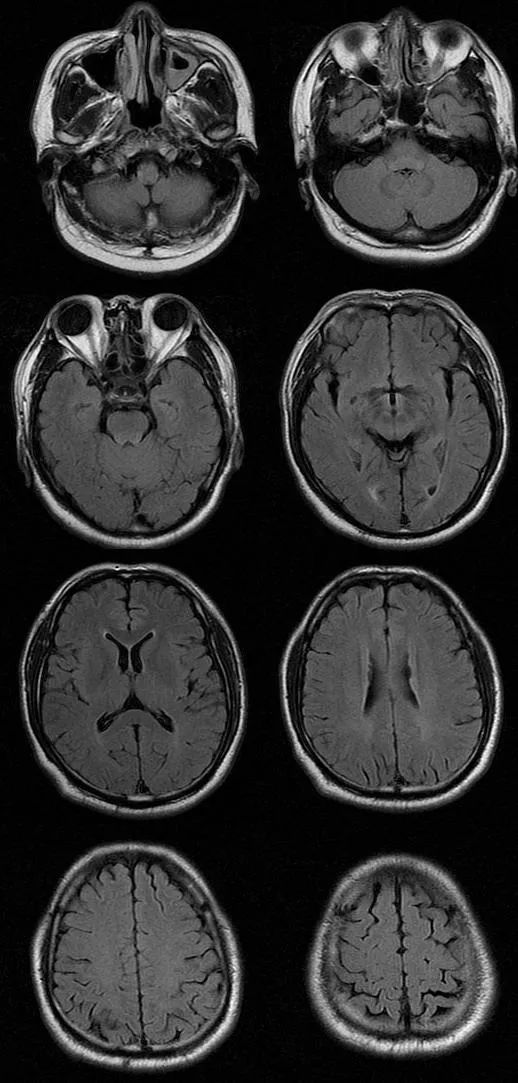

遗憾的是胸腰部 MRI 中 T1、T2、STIR 均未见明显异常,我们进一步完善头部 MRI,如下图:

T2FLAIR

从影像学可以看出 T2FLAIR、T1、T2 似乎也未见明显异常,此时该如何诊断,定位到底在哪里呢?